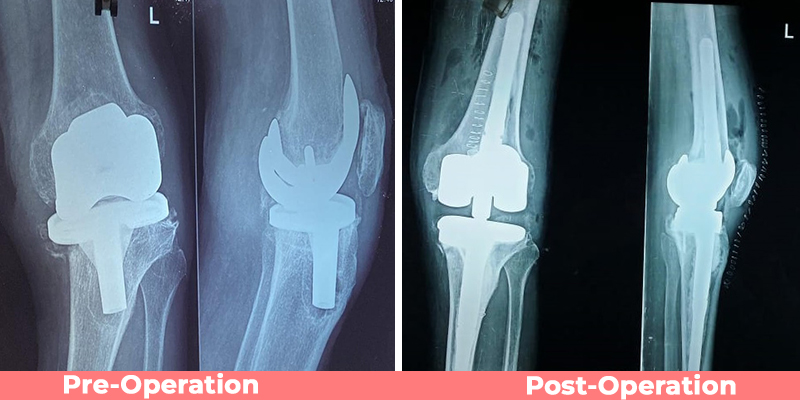

Complex Knee Replacement Surgery

Dr. Rajesh Sharma

Successful treatment of advanced arthritis with robotic-assisted surgery.